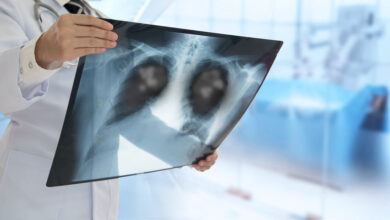

Cáncer de pulmón

Cáncer de pulmón de células no pequeñas: crecen tasas de supervivencia

Cáncer de pulmón: La importancia de la detección temprana

¿Qué tan común es el cáncer de pulmón y a quiénes afecta?

Estos son los exámenes que permiten detectar el cáncer de pulmón